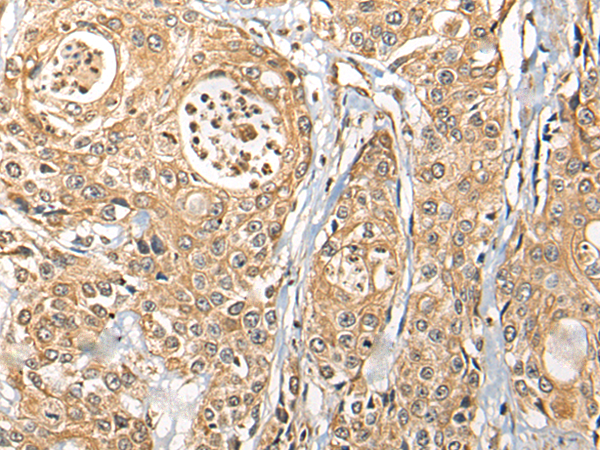

IHC positive control: |

Human prostate cancer |

IHC Recommend dilution: |

25-100 |